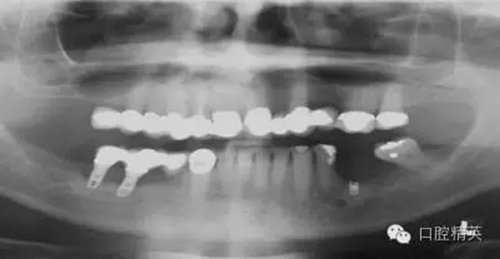

圖2a:術(shù)后曲面斷層片顯示兩顆種植體分別異位于左右側(cè)上頜竇中

另一個(gè)和醫(yī)生僅用兩維放射線檢查造成的特殊并發(fā)癥是種植體進(jìn)入上頜竇。(圖2a-c)可能成為上頜竇異物的有牙齒,牙根,印模材料,牙科器械,近年來又增加了一個(gè)—種植體??上攵瑥纳项M竇中取出異物對(duì)患者來講是創(chuàng)傷很大的。

其他研究也報(bào)道過,對(duì)于這種病例,唯一的選擇是用根管顯微鏡或Caldwell Luc技術(shù)從上頜竇中取出種植體。有些文章報(bào)道了如何處理進(jìn)入上頜竇的種植體,但很少?gòu)念A(yù)防的角度來談這個(gè)問題,其實(shí)很簡(jiǎn)單,術(shù)前應(yīng)該應(yīng)用CBCT成像檢查。